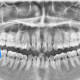

Pasien perempuan usia 25 tahun datang dengan keluhan mulut sulit terbuka dan terasa nyeri sejak 2 hari terakhir. Setelah dilakukan rontgen gigi ditemukan gambaran ini. Menurut dokter, apa yang dapat terjadi kepada pasien?

Dari pemahaman saya sebagai dokter umum, gigi pasien terjadi impaksi di gigi 48,

Betul sekali 48 impaksi dan karies, kondisi itu bisa menyebabkan trismus/susah membuka mulut ( normalnya buka mulut itu 3 jari ( jari telunjuk, jari tengah, jari manis bisa masuk dlm mulut pas posisi buka mulut). Kondisi hanya impaksi saja bisa menyebabkan trismus, apalagi ini ditambah karies. Sebaiknya periksa ke spesialis bedah mulut untuk penanganan lebih lajut ( dilakukan OD ), untuk mengatasi trismusnya. Semoga bisa membantu menjawab, terima kasih

tampak nekrosis pulpa

rekomendasi utk dilakukan odontektomi utk mencegah infeksi dan nyeri